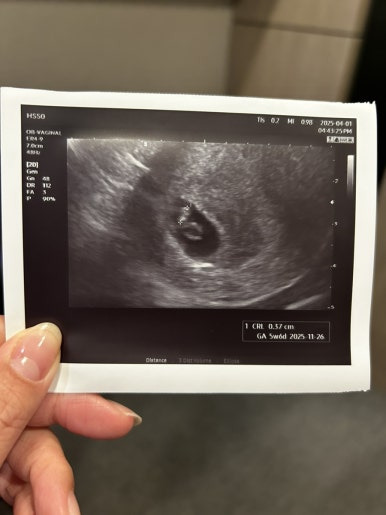

이 시기에만 볼 수 있다는 다이아몬드💍

화질이 엄청 선명하진 않지만

난황도 잘 커졌고, 그 위에 예쁘게 자리잡은 사탕이

사탕이는 그새 커서 0.37cm가 되었다👼🏻

(주기는 좀 밀려 5주로)